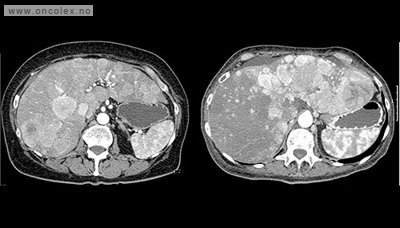

Før operasjonen utredes leveren ved CT eller MR. Sandostatin® gis før inngrepet. Dette er et syntetisk framstilt medikament som har samme virkning som somatostantin, som hemmer frigjøring av hormoner og utskillelse av sekret fra blant annet galleblæren.

Etter operasjonen kontrolleres pasienten med CT eller MR. Dette gjøres vanligvis 6 måneder etter inngrepet.